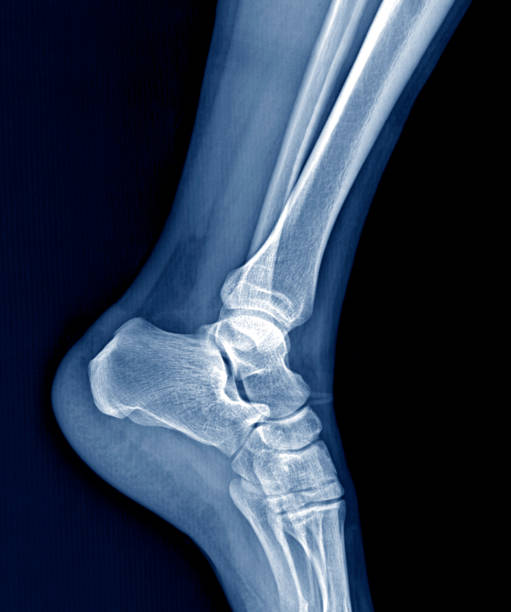

발뒤꿈치가 아픈 이유 5. 발목 터널 증후군

발뒤꿈치가 아픈 이유 다섯 번재는 발목 터널 증후군입니다. 내측 복사뼈와 발뒤꿈치 뼈 사이의 족근관을 관통하는 후경골 신경이 눌리거나 손상되면 저림, 작열감 등을 느끼게 됩니다. 이때는 신경 압박에 의한 통증이기 때문에 앞서 언급한 연조직 손상과 달리 통증의 위치가 명확하지 않고 신경 경로를 따라 퍼지는 특성을 갖고 있습니다.